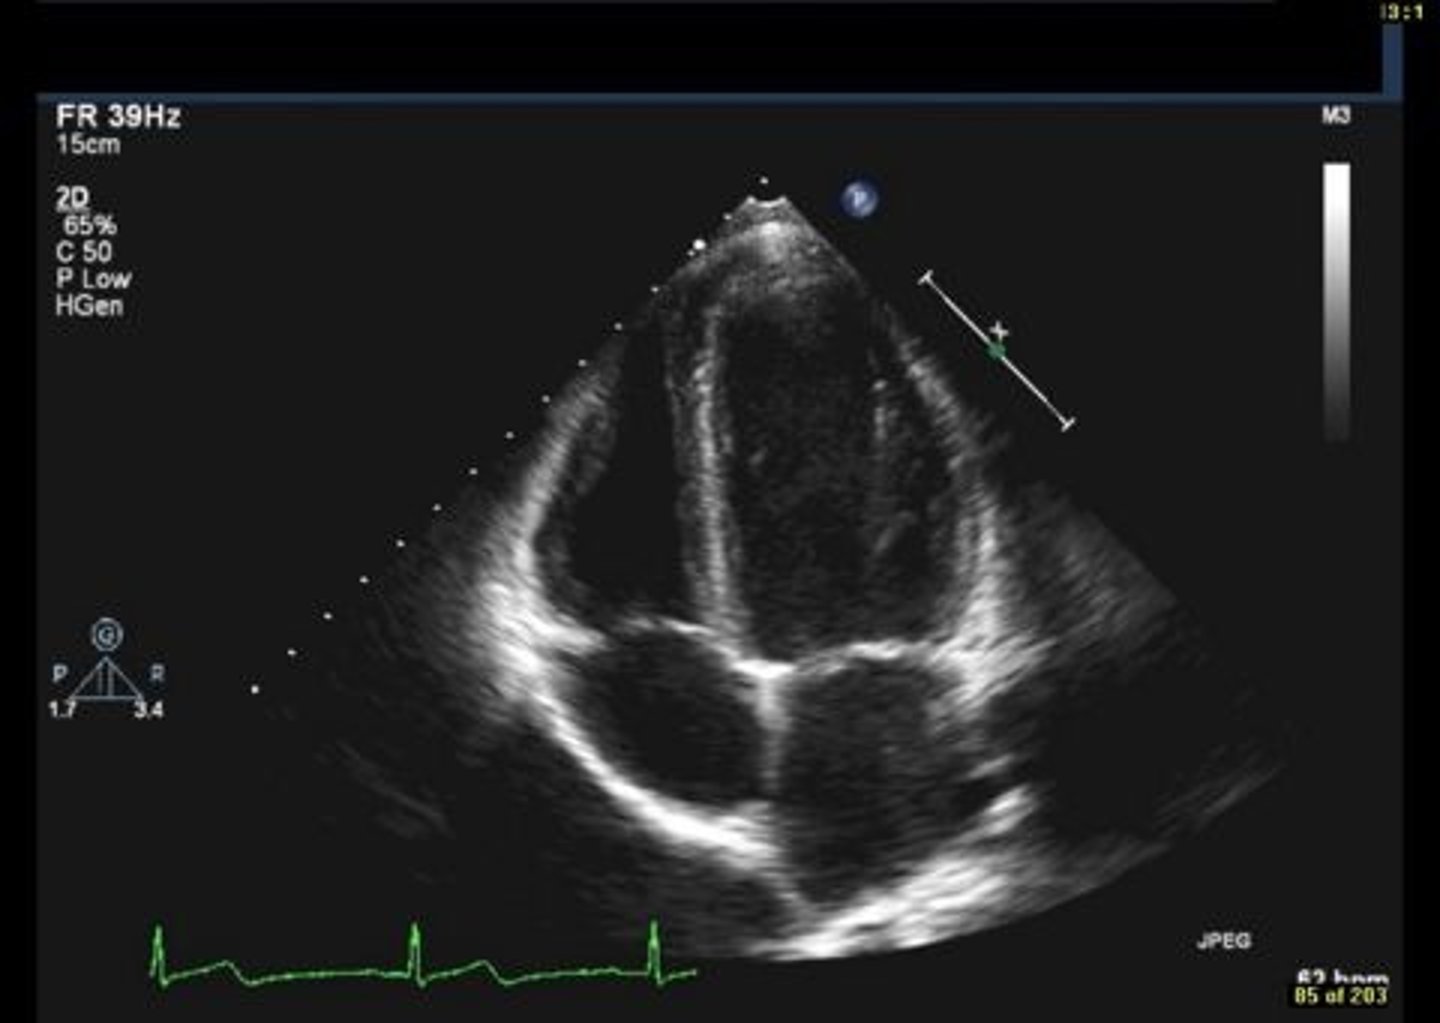

anterior mitral valve leaflet

top leaflet

posterior mitral valve leaflet

bottom leaflet